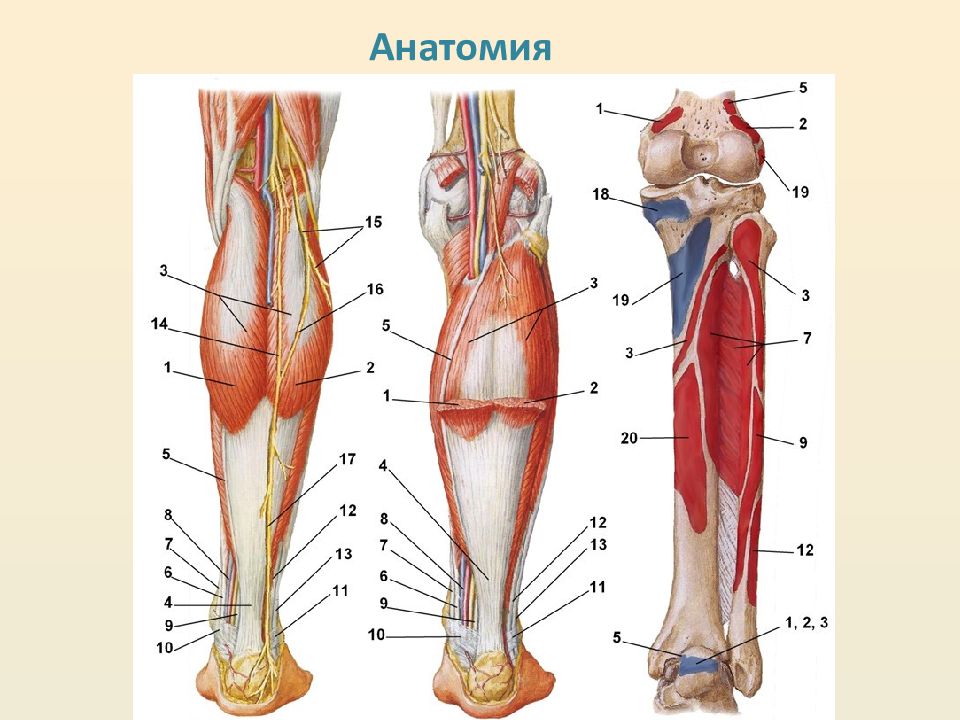

Анатомия подошвенной мышцы голени: подробное рассмотрение